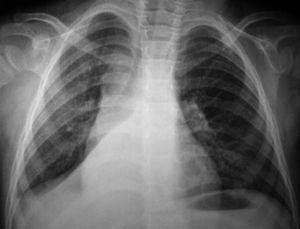

A los niños con Mantoux positivo se les realizó una radiografía de tórax que fue patológica en 10 de los 11 (90,9 %) que fueron derivados a nuestro hospital. El niño sin alteraciones radiológicas recibió profilaxis con isoniazida durante 9 meses. La edad media fue de 23,1 meses (11-42 meses). De estos 10 niños, siete estaban sintomáticos en el momento del estudio, cinco presentaban tos, cinco fiebre y uno eritema nudoso (tabla 1). Las imágenes radiológicas mostraron condensación parenquimatosa en el 90 % de los pacientes y adenopatía parahiliar en el 50 % (figs. 1-3).

Figura 2. Paciente n.º 1 (evolución). Atelectasia del lóbulo inferior derecho.

Los 10 pacientes con radiografía patológica iniciaron el tratamiento con isoniazida, rifampicina y pirazinamida. Siete pacientes presentaron una buena evolución no precisando otros tratamientos ni exámenes complementarios. Sin embargo, en 3 niños se observaron alteraciones de la ventilación en la radiografía de tórax en forma de atelectasia al inicio del tratamiento. En estos niños se practicó una broncoscopia y se añadieron corticoides al tratamiento tuberculostático. Los 3 niños tuvieron buena evolución. Al finalizar el tratamiento de 6 meses, todos los niños estaban asintomáticos y con normalización de las imágenes radiológicas. La estancia media en el hospital fue de 5 días. No se detectaron casos de tuberculosis en los miembros de la familia de los niños enfermos.

En pacientes pediátricos, la presencia de linfadenopatía hiliar, mediastínica o cervical, afección pulmonar con infiltrados segmentarios o lobulares, neumonía consolidada, atelectasias, derrame pleural o tuberculosis miliar representan el espectro de enfermedad en este grupo de población 32. En nuestros casos la forma de presentación más frecuente fue la consolidación pulmonar seguida de adenopatías hiliares y atelectasia pulmonar.

Las lesiones pulmonares tuberculosas se encuentran con mayor frecuencia en el pulmón derecho (55 %). En nuestro estudio, de los niños que presentaban imágenes de condensación parenquimatosa, cuatro se localizaron en el pulmón derecho y cinco en el izquierdo. De preferencia las lesiones se localizan en las porciones mejor ventiladas, parte baja del lóbulo pulmonar superior y alta del inferior. Muy raras veces en el vértice. En la mayoría de los casos, el foco es único, raras veces doble 33.